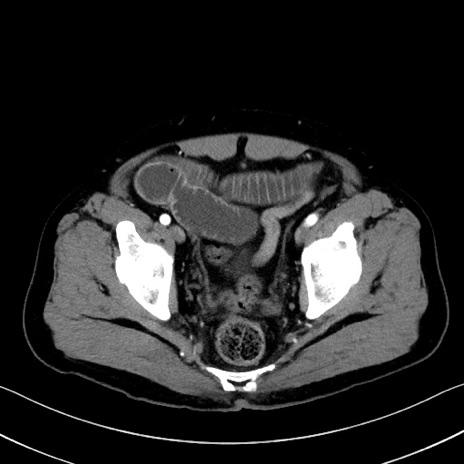

症例35(横断像)

【症例】70歳代 男性

【主訴】腹部膨満、嘔吐

【現病歴】昨日より腹部膨満感出現。本日増悪し、仙痛出現。嘔吐あり、受診。

【既往歴】糖尿病、胆摘後

【身体所見】BP 149/80mmHg、HR 74/min、BT 35.9℃、腹部:膨満、軟、圧痛なし。腸雑音減弱あり。上腹部正中切開瘢痕あり。

【データ】WBC 13500、CRP 1.72